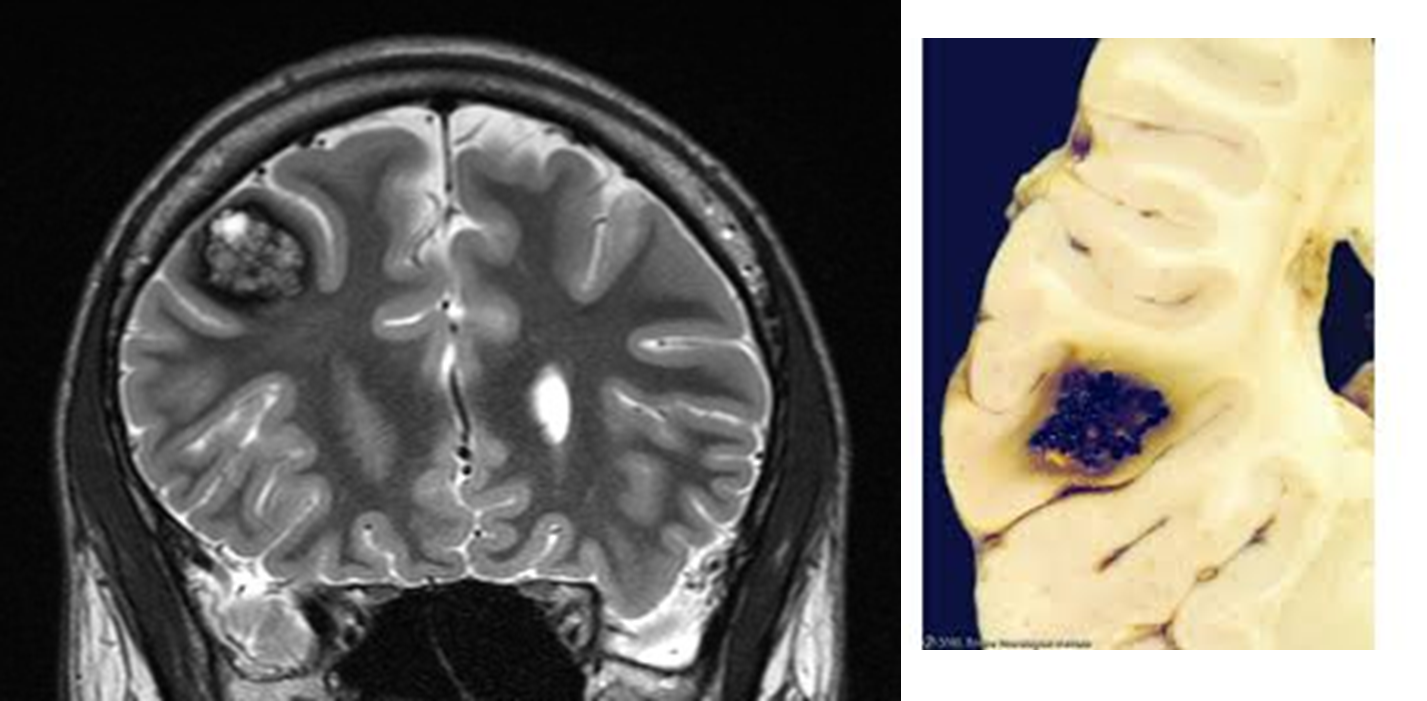

What are Cavernous Malformations

Cavernous malformations are a form of vascular malformation that can lead to intraparenchymal hemorrhage

1) causes tufts of dilated thin walled capillaries

→ opposed to arteriovenous malformations, there is no feeding arteries or draining veins

Arteriovenous malformations are congenital vascular malformations that can result in intraparenchymal hemorrhages

1) AVMs are congenital malformations where there is a direct connection between arteries and veins without a intermediate capillary bed

→ gliotic, or glial cells, are often mixed in with the vascular tissue